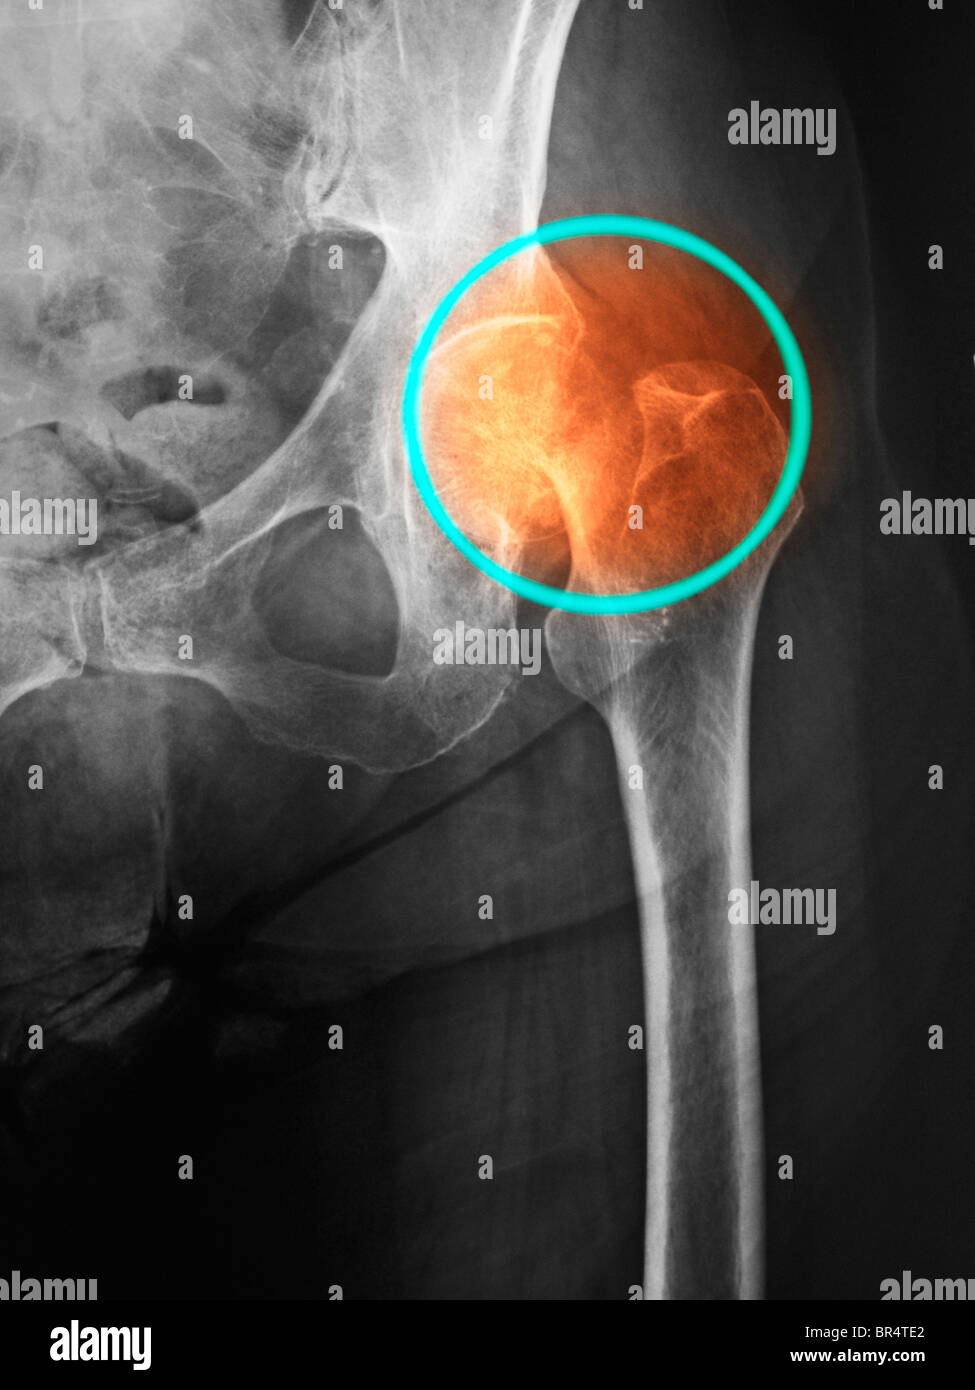

xray of a hip fracture in a 85 year old man, Hip fracture in an 85 Hip Fracture Xray learn about hip fractures, a break in the upper part of the thighbone that can be very painful and require surgery. learn about the causes, classification, diagnosis and treatment of neck of femur fractures, a common injury in elderly. The series is requested for a. proximal femoral fractures are a subset of fractures that occur in the. Hip Fracture Xray.

From www.alamy.com